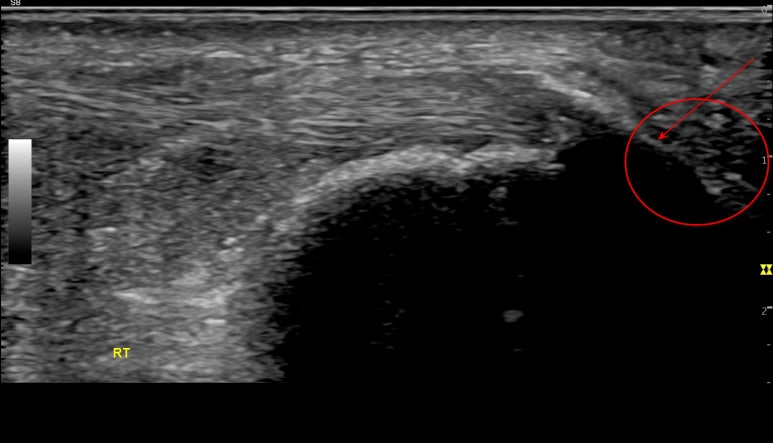

아킬레스건 석회화

아킬레스건 염증으로

힘줄에 상처가 나고 아물면서

상처 부위에 딱지 지듯이

칼슘이 들러붙기도 합니다.

이를 이라고 하는데요.

아킬레스건은

혈액순환이 잘 되지 않아

이런 석회 돌 조각이

흔히 생깁니다.

두번째 환자분은

경기도 일산에서 오신 분인데요.

표준 초음파 영상과 달리

이 환자분 영상의

친 곳에

하얀 돌 표면이 보입니다.

침을 놓을 때

힘줄 안에 석회를

세게 찌르면

칼슘이 흡수되면서

염증을 일으키게 됩니다.

가뜩이나 염증으로 아픈데

침 맞고 더 아프실 수 있거든요.

안전하고 정확한 침 치료를 위해

반드시 초음파로 체크해봐야 합니다.